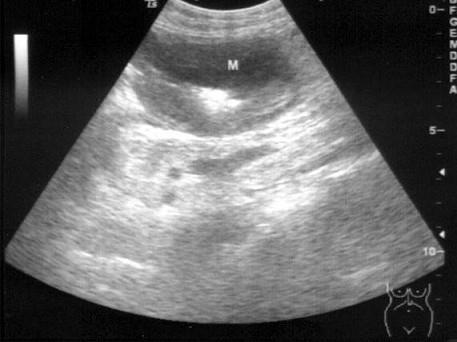

问题 患者男65岁,上腹部疼痛3个月余,进行性加重1周余,进食后呕吐。上腹部B超检查如图所示,根据超声声像图诊断为?(?)

选项 A.胃溃疡 B.胃炎 C.胃癌 D.肝癌 E.胰头癌

答案 C